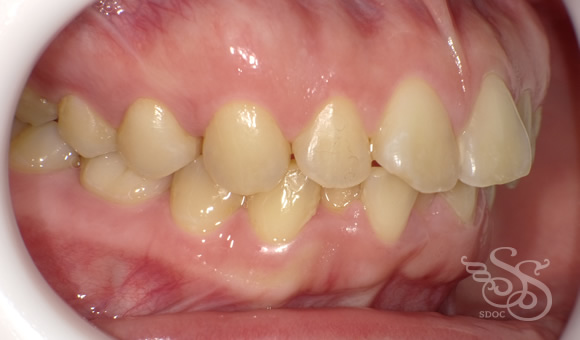

右側:術前

Bi-max症例ですね。

よく抜かないで矯正をすると

こんな感じにフレアーアウトしたフィニッシュになりがちですね。

あと、この患者さまは

下顎5番の 先欠でEが残存していました。

乳歯は後継永久歯がなくても

根は吸収していきますので

いつかはダメになります。